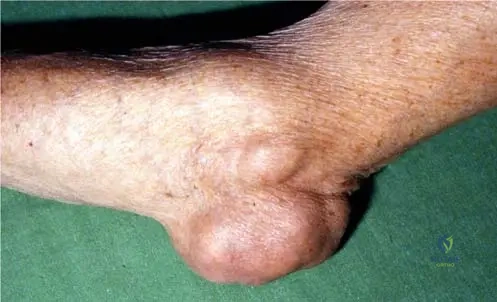

A 70-year-old male with a long history of gout presents with a large, firm, non-tender mass over his left elbow. Examination reveals significant swelling and a palpable nodule in the olecranon region. This finding is consistent with a massive tophaceous deposit of urate crystals. Which image best illustrates this specific presentation?

Rationale: Fig. 7.9 is explicitly labeled "Bursitis olecrani due to the massive tophaceus deposit of urate crystals." This perfectly matches the clinical vignette describing a tophaceous mass over the olecranon. The other images depict chronic hand gout, subcutaneous tophi in the palm, acute knee gout, or intraoperative findings, not specifically olecranon bursitis.

During surgical excision of a large tophus from the elbow of a 68-year-old male with chronic gout, the surgeon encounters a distinctive mass. What is the characteristic gross appearance of a gouty tophus as observed intraoperatively?

Rationale: The clinical context for Fig. 7.10 a states, "The intraoperative picture demonstrates the encapsulated yellow chalky mass of gouty tophi." This directly describes the gross appearance. The other options describe features inconsistent with gouty tophi.